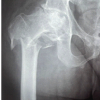

Three patients (Fig. 1) initially received an uncemented titanium stem, a titanium threaded cup with an inclination between 40 and 45°, standard ultra-high-molecular-weight-polyethylene inlays, and a 28 (n = 1) or 32 mm (n = 2) TiN-coated head. In all cases, the acetabular component was to be revised due to definite aseptic loosening (Pinnacle® cup: Sector II n = 2, Multihole n = 1). Marathon® liners and Articul/eze® (CoCr; Arge) heads were used in all instances for revision, expect for Case 3.

Case 1 (female, 76 years) has had minimal osteolysis around the proximal stem with no loosening, and thus, the femoral implant was retained. The initial diagnosis for THA was primary osteoarthritis. The revision-free interval was 9.5 years (07/00–01/10). Case 2 (male, 56 years) has had femoral osteolysis Type II (Paprosky) of the well-fixed stem 10.9 years (06/01–05/12) after THA due mild dysplasia and was treated with bone grafting of the proximal defects (15 cm3).

Case 3 (male, 47 years) has had more extensive osteolysis affecting the ischium and pubis (type IIIa) with severe metallosis and sander marks on the head’s surface. Metal wear was seen in the histologic samples. Extensive bone grafting of the defects in the ischium (12 cm3) and pubis (8 cm3) was necessary. The stem was clinically loose at surgery and was revised using a solution stem (DePuy) through an extended trochanteric osteotomy, plus a trochanteric grip plate due to refixation of periprosthetic trochanteric fracture (Trofix®, Zimmer, Fig. 1b). The primary surgery was 10.0 years ago (01/02–12/11). Retrieved implants demonstrated significant volumetric wear of the liner (up to 2.84 cm3) with either partial or complete loss of the TiN coating and volumetric wear of the TiALV-heads. In all three cases, the TiN coating was delaminated to varying but significant extents. No backside wear or liner damage was noted. Measurements were done by three independent blinded assessors and averaged. An electronic digital caliper (digiMax, Swiss Precision Instruments, Inc.,) was used. The damaged femoral head coating ranged 0.5 cm2 (elderly patient) to 5.75 cm2 (two younger patients, Fig. 1). The two younger patients also had a defect of the TiALV head itself. All defects were palpable. The head diameter was reduced by 0.19 mm (32 mm head) and 0.18 mm (28 mm head). Histologically, a range of mild to severe metallosis was found in three cases in addition to wear-induced synovitis [4,5]. All patients suffered from mainly load depending hip pain without neurological symptoms.